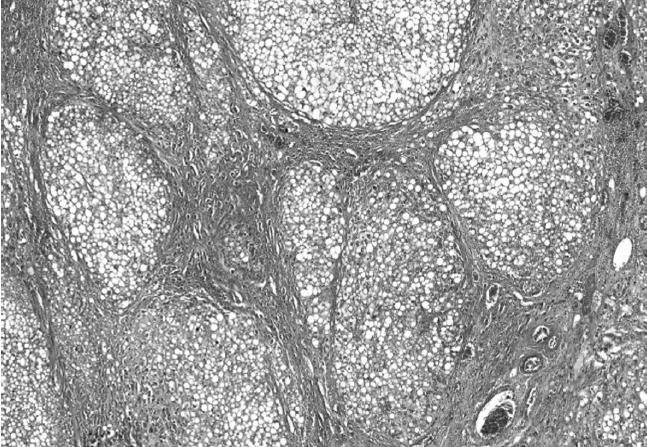

Во всех исследуемых случаях на фоне выраженных дистрофических изменений в ткани печени отмечались разной степени выраженности склеротические изменения стромы: от разрастания рыхлой, нежноволокнистой соединительной ткани вокруг центральных вен с незначительным расширением портальных трактов до выраженного перипортального и центролобулярного перивенулярного фиброза, а также местами перицеллюлярного фиброза. В 19 % исследуемых случаев (18 женщин, 11 мужчин) в ткани печени мы наблюдали выраженную перестройку структуры ткани печени вследствие формирования портального цирроза печени. В исследуемых образцах ткани печени отмечалось вклинение в печеночные дольки тонких фиброзных септ из расширенных фиброзированных перипортальных полей с последующим соединением центральных вен с сосудами портальных трактов и образованием мелких ложных долек, состоящих из пролиферирующих гепатоцитов в состоянии жировой и белковой дистрофии с отсутствием радиальной ориентации печеночных балок (рис. 3).

Рис. 3. Цирроз печени с формированием ложных долек, состоящих из гепатоцитов в состоянии выраженной жировой и белковой дистрофии (окраска гематоксилином и эозином, ув. ×100)